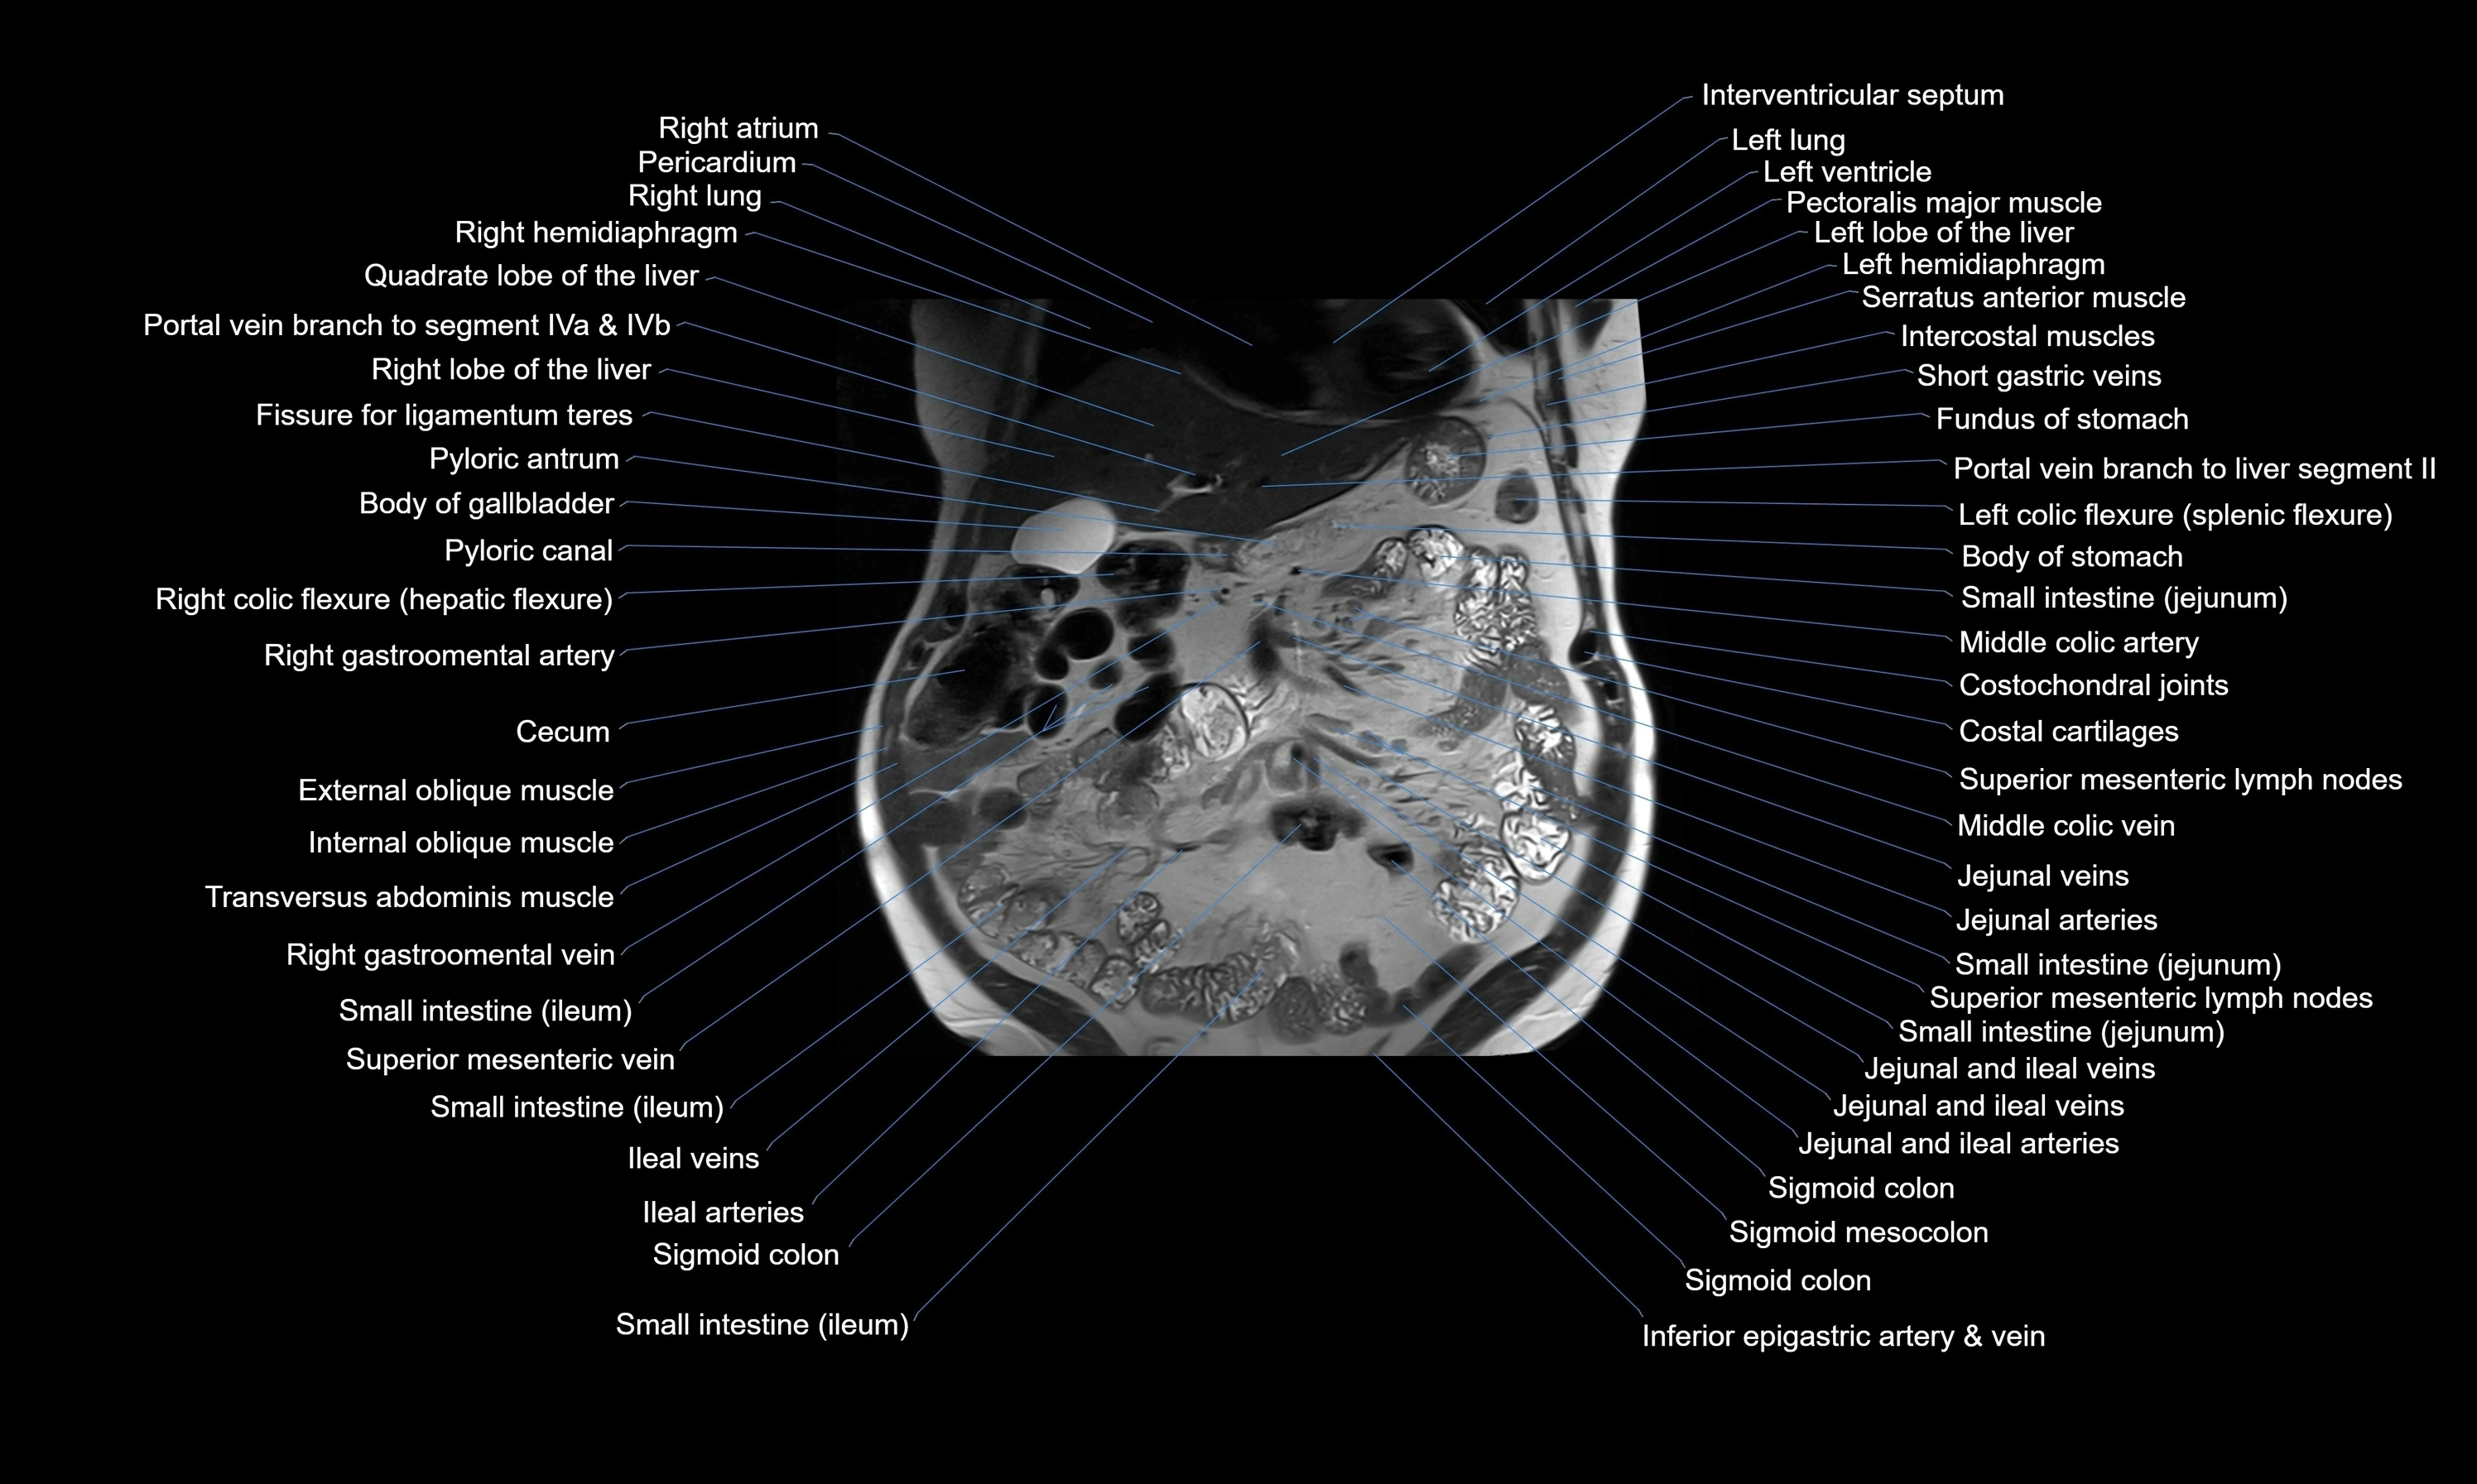

MRI images